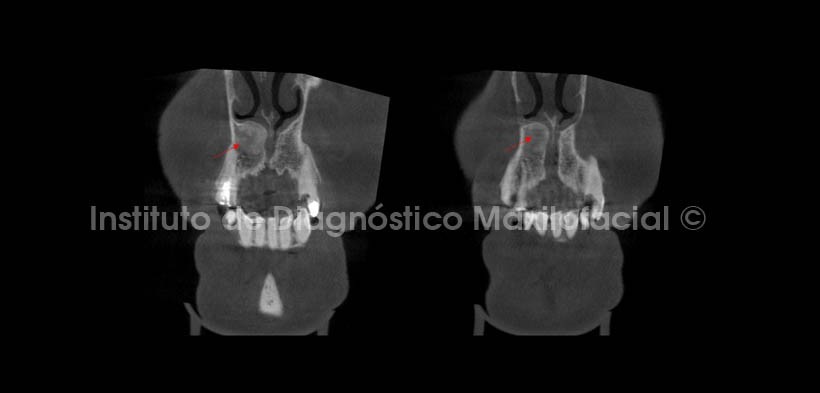

Se realizaron cortes multiplanares; en los cuales se observa el leve estrechamiento del conducto nasopalatino en su porción más superior en el corte coronal (Fig. 3), además del mencionado desplazamiento cefálico del piso de fosa nasal del lado derecho. En cortes axiales (Fig. 4), se aprecia el ocupamiento de la parte anterior de la fosa nasal derecha condicionado por el crecimiento de la lesión, observando la cercanía de esta con la espina nasal anterior, y en cortes sagitales (Fig. 5) se evidencia un leve desplazamiento de la tabla ósea vestibular.